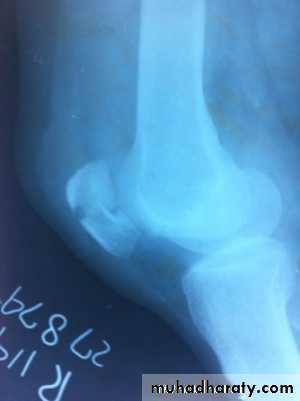

Dislocation of the patella

Clinically :

The knee collapses and patient fall on ground. Patella can be felt on outer side of knee or the patella springs back into position spontaneously. The X- ray shows dislocation of patella laterally and associated fractures if present.